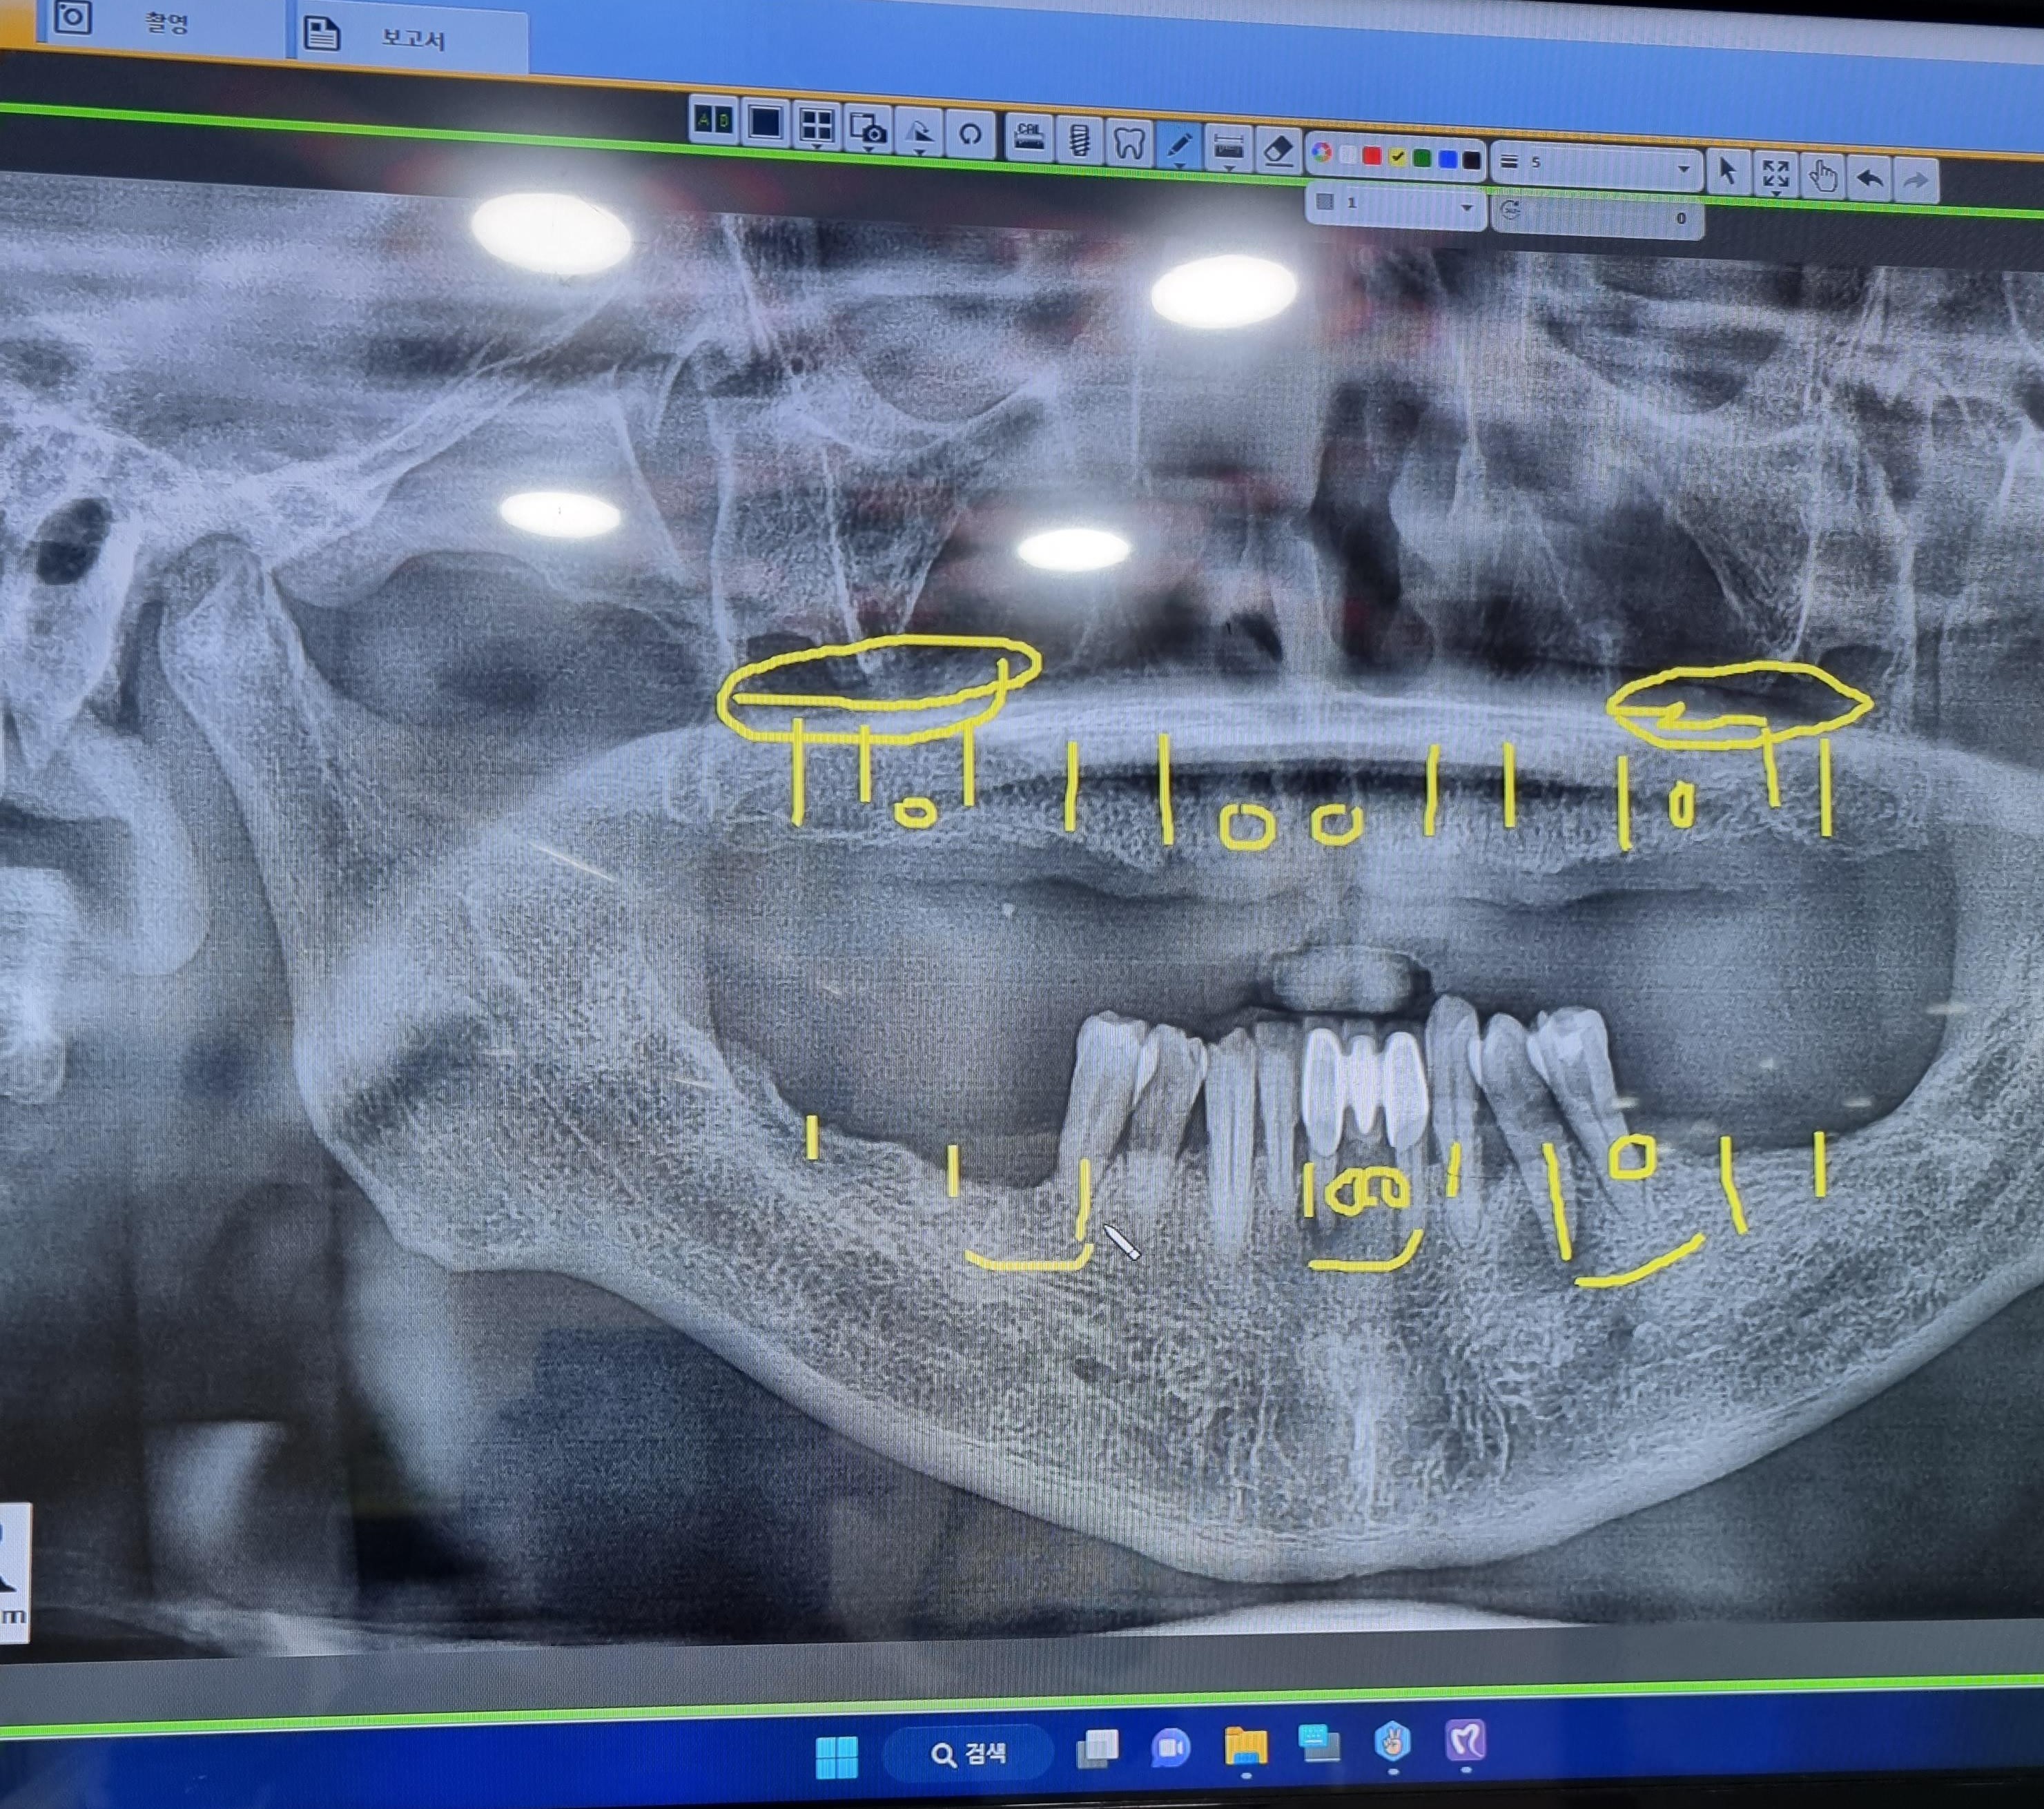

CT 촬영을 통해 구강口腔健康내  상태등을  검사하고  윗턱의  경우  모두  치아齒牙

치주염 齒周炎으로 인하여 결손된 상태라서 자연치아齒牙 2개와

전체  임플란트dental implant와  브릿지bridge를 같이  결합하여

전체  임플란트dental implant의 개수를  낮추는 방향으로  진행 하엿습니다.

임플란트dental implant를  윗니上顎 Over Denture 10   아랫니 下顎 치아齒牙 2 개를

제외하고 대부분의  치아齒牙  치주염 齒周炎 으로  좋지않은  상황이라

발치拔齒 뼈이식과  임플란트 8개를 식립植粒하기로 했습니다.

임플란트dental implant 18개을 식립植粒하는  수술이고.

1 上顎 Over Denture 76 X  32 X   X 23    4 X 67    10

下顎 765       1      XX 3   4 X 67      8

상악上顎 13.12.22.23.24.26.27 뼈이식과 인공치근 식립植粒 함께  진행하였습니다.

오늘은 윗니上顎 우축 14.16.17 치조골이식술을  동반한  인공치아  식립植粒술이 진행하였습니다.

1차  아랫니下顎 우축 1개을  발치와 45.48.47뼈이식 3개의 임플란트dental implant식립植粒 수술을  하였습니다

아랫니下顎  앞니 브릿지1개를  포함하여 32.33.41.42 4개의 치아를  쪼로록록  발치拔齒와  33.42 .

임플란트dental implant 2개 식립植粒 하는  수술이 완료  되었습니다